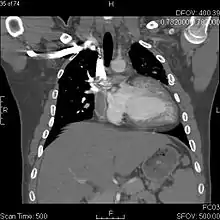

The Fontan procedure or Fontan–Kreutzer procedure is a palliative surgical procedure used in children with univentricular hearts. It involves diverting the venous blood from the inferior vena cava (IVC) and superior vena cava (SVC) to the pulmonary arteries. The procedure varies for differing congenital heart pathologies. For example in tricuspid atresia, the procedure can be done where the blood does not pass through the morphologic right ventricle; i.e., the systemic and pulmonary circulations are placed in series with the functional single ventricle. Whereas in hypoplastic left heart syndrome, the heart is more reliant on the more functional right ventricle to provide blood flow to the systemic circulation. The procedure was initially performed in 1968 by Francis Fontan and Eugene Baudet from Bordeaux, France, published in 1971, simultaneously described in 1971 by Guillermo Kreutzer from Buenos Aires, Argentina, and finally published in 1973.[1][2]

The Fontan Kreutzer procedure is used in pediatric patients who possess only a single functional ventricle, either due to lack of a heart valve (e.g. tricuspid or mitral atresia), an abnormality of the pumping ability of the heart (e.g. hypoplastic left heart syndrome or hypoplastic right heart syndrome), or a complex congenital heart disease where a bi-ventricular repair is impossible or inadvisable. The surgery allows blood to be delivered to the lungs via central venous pressure rather than via the right ventricle.[3] Patients typically present as neonates with cyanosis or congestive heart failure.[4] Fontan completion is usually carried out when the patient is 2–5 years of age, but is also performed before 2 years of age.[5][6]

The third stage is called the Fontan procedure which involves redirecting the blood from the inferior vena cava to the lungs.[8] At this point, the oxygen-poor blood from upper and lower body flows through the lungs without being pumped (driven only by the pressure that builds up in the veins or central venous pressure). This improves the lower than normal oxygen levels and results in one functional ventricle that is responsible for supplying blood to the rest of the body. There are currently three various modern techniques for the Fontan procedure which include: Atriopulmonary connection, lateral tunnel total cavopulmonary connection, and extracardiac conduit.[15]